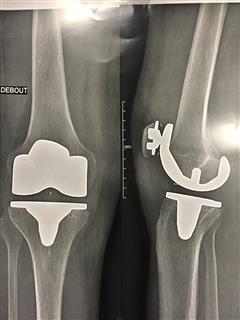

radio genou prothèse

ou alors il y a cela !!!!!